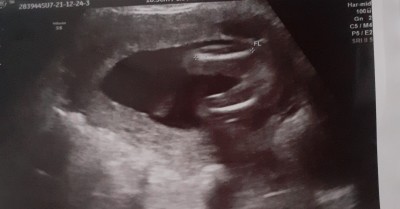

Anlayamadim kizmidir

Cinsiyet tahmini

17 hafta 6 günlük

kız hiç bir çıkkınlık yok

Doktor soylemedimi bu ultrason kağidından sadece dr anlar bence

Yuzde 50 kız dedi

Kesinlikle kız olarak görünüyor hayırlısını nasip etsin inşallah kız erkek farketmez tabii ki